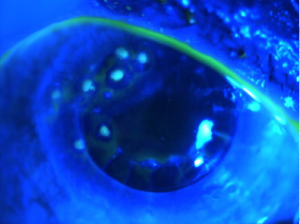

The diagnosis of SND is usually made clinically. A slit lamp exam can show the characteristic gray, white, or bluish nodules posterior to the corneal epithelium.[9] These nodules can occasionally stain with fluorescein (Figure 2).[3] Corneal topography can reveal significant irregular astigmatism occurring as a result of Salzmann nodules (Figure 3).[9]

These patients usually present with gradual, painless loss of vision—both near-vision and distance-vision.[9] They may or may not have a history of chronic ocular surface disease such as that described above. Patients may also complain of a “foreign body sensation” on the surface of their eye.[4] Slit lamp exam can reveal white to bluish-grey nodules within the cornea (Figure 4).[4]